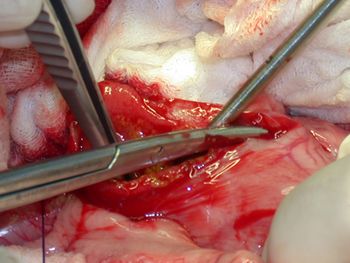

Try this tip for avoiding tears when removing thin, linear intestinal foreign bodies.

Practical pointers from a hands-on course on performing common gastrointestinal surgeries.